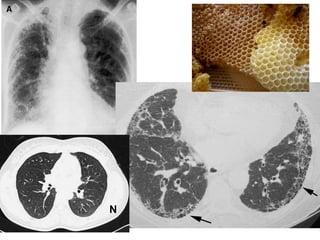

Usual Interstitial Pneumonia (UIP) PatternUsual Interstitial Pneumonia (UIP) Pattern

High Resolution

Computed Tomography (HRCT)

1) Subpleural, basal predominance.

2) Honeycombing.

3) Reticular pattern.

4) Absence of features of

alternative diagnosis, eg,

- Upper or mid lung

predominance.

- Segmental or lobar

consolidation.

Histopathology

1) Marked fibrosis + honeycombing

in a predominantly subpleural

distribution.

2) Patchy pulmonary fibrosis.

3) Fibroblast foci.

granulomas, infection.

• #8 Plain X-Ray chest: Early: ground glass Late: honeycomb